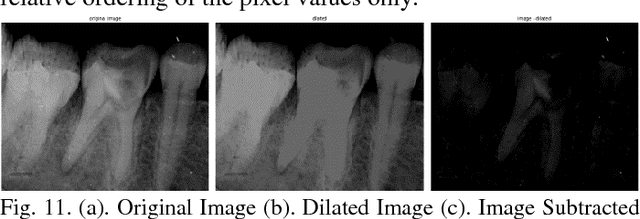

With the recent advancements in Image Processing Techniques and development of new robust computer vision algorithms, new areas of research within Medical Diagnosis and Biomedical Engineering are picking up pace. This paper provides a comprehensive in-depth case study of Image Processing, Feature Extraction and Analysis of Apical Periodontitis diagnostic cases in IOPA (Intra Oral Peri-Apical) Radiographs, a common case in oral diagnostic pipeline. This paper provides a detailed analytical approach towards improving the diagnostic procedure with improved and faster results with higher accuracy targeting to eliminate True Negative and False Positive cases.